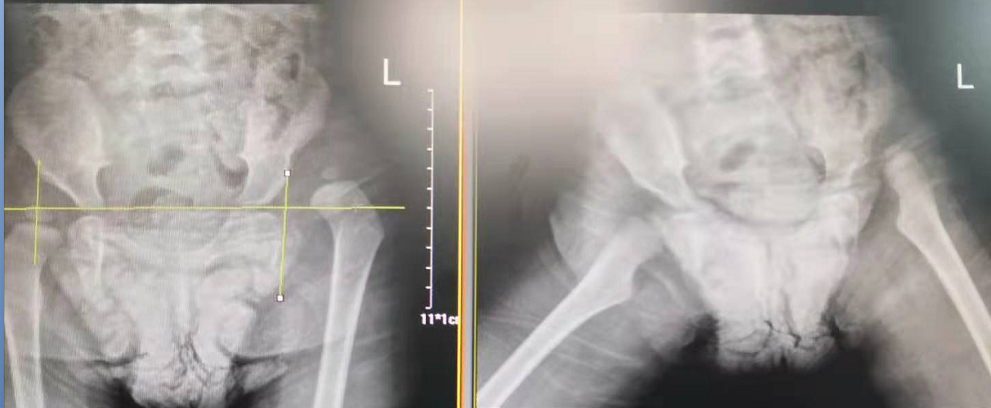

2歲零1個(gè)月的幼兒玥玥(化名)因先天性髖關(guān)節(jié)脫位(也就是我們常說(shuō)的“長(zhǎng)短腿”)來(lái)到了瀘州市中醫(yī)院治療。在醫(yī)院骨傷三科岐黃名中醫(yī)、副主任中醫(yī)師鄭磊的帶領(lǐng)下,科室與麻醉科密切配合,順利為玥玥實(shí)施了手術(shù)。

術(shù)前

術(shù)后

據(jù)了解,玥玥的左腿比右腿要短3厘米,導(dǎo)致她走起路來(lái)“不對(duì)頭”:一拐一拐的,像小鴨子走路一樣。